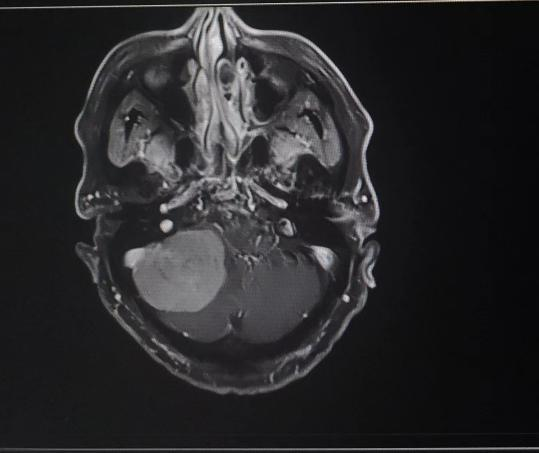

患者入院后,头颅MR检查后发现,小脑右侧长了巨大肿瘤,直径约6公分,患者家属收到不小的惊吓。患者4年前曾做过一次头颅核磁共振,当时肿瘤较小,考虑到患者已经88岁,家人还是决定保守观察,没想到如今,它已经长大到足足有一个土豆那么大,而且患者头晕较重,反复恶心、呕吐,卧床不起,因此必须进行手术,才能解决患者病症。